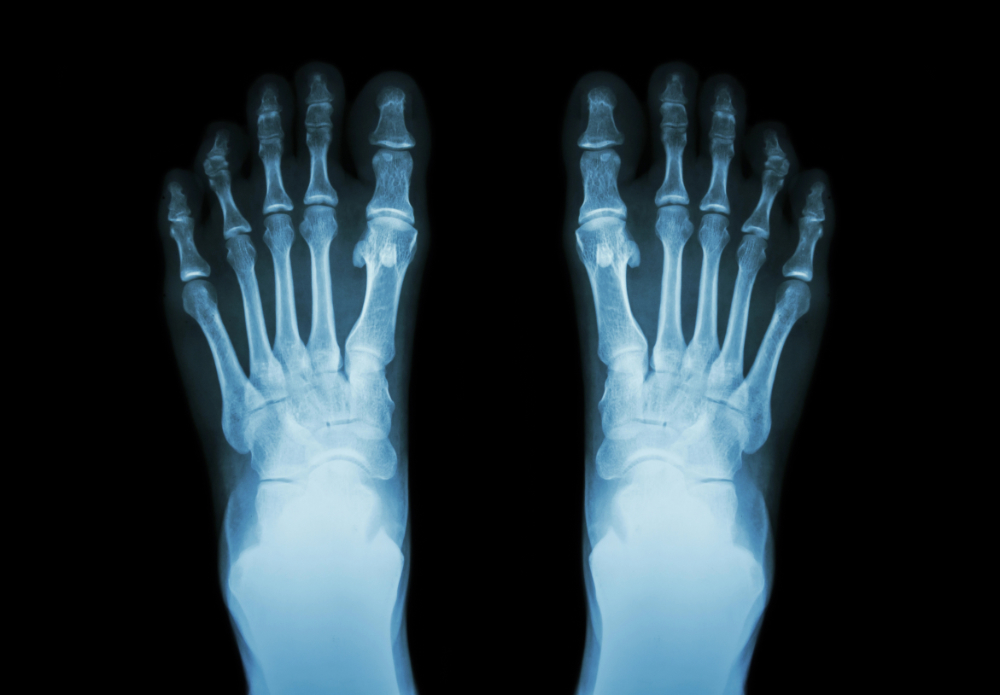

Digital X-rays - Unlike traditional film, digital X-rays provide high-resolution images instantly with less radiation exposure. They allow your podiatrist to zoom in on micro-fractures or subtle bone changes.

Most appointments include diagnostic imaging. Once the diagnosis is confirmed, the doctor will build a plan. At Elgin clinics, the focus is typically on a conservative-first approach, and podiatrists will explain why you are hurting and how the proposed treatment solves the problem.

Follow-up X-rays to check bone healing.